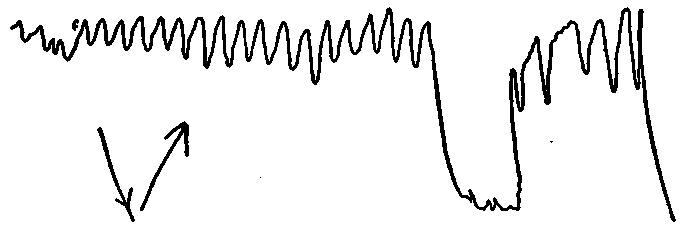

| 23. | Normal diaphragm curve in normal breathing | 577 |

| 24. | Curve in diaphragm before and during talking by a stutterer | 577 |